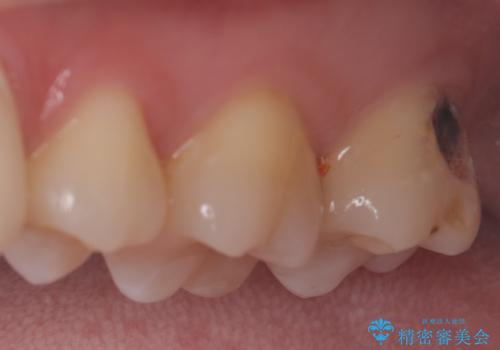

- セラミッククラウン

- 2009~2025年6月

- 000本

- セラミックインレー